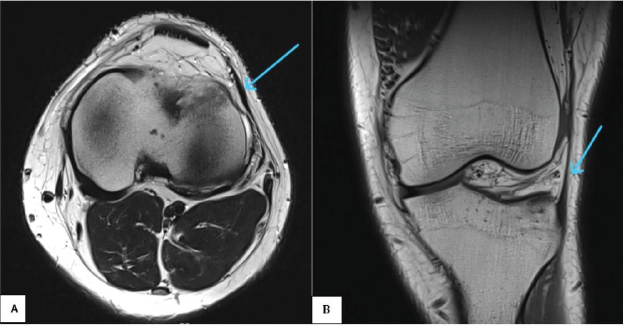

There was no significant finding on plain X-ray of the left knee in orthogonal views. MRI of the left knee demonstrated linear thickening of the lateral patellar retinaculum extending from the inferolateral patellar border to the lateral aspect of the proximal tibia (near tibial tubercle), corresponding to the LPTL. The LPTL appeared thickened in comparison to its medial counterpart. Associated bone marrow edema was noted at the anterolateral tibial cortex adjacent to Gerdy’s tubercle, precisely at the site of ligamentous attachment. On MRI, the marrow edema was seen as a hyperintense signal on T2-weighted (Fig. 1) and proton density fat-suppressed (PDFS) sequences (Fig. 2), with corresponding hypointensity on T1-weighted images. The signal alteration was limited to the subcortical marrow without evidence of cortical breach, fracture line, or intraosseous cyst formation. These findings are consistent with enthesopathic stress-related changes at the tibial insertion of the LPTL and correlated well with the patient’s localized pain and tenderness. The cruciate ligaments, collateral ligaments, menisci, and articular cartilage were all intact, and no joint effusion was observed.

Figure 1: Axial (a) and coronal (b) T2-weighted magnetic resonance imaging images of the left knee joint show focal thickening of lateral patellar retinaculum (sky-blue arrow), which is classically described as the lateral patellotibial ligament.